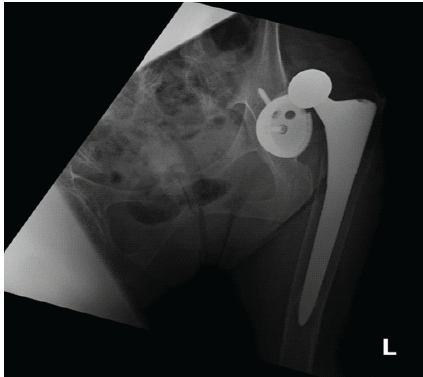

An 87-year-old female with a medical history of dementia, hypertension, and hyperlipidemia underwent a left THA through a posterior approach in 2010. She presented to the emergency department following a ground-level fall, reporting severe left hip pain and an inability to bear weight. Imaging confirmed a left periprosthetic hip dislocation (Fig. 1).

Figure 1: Pre-reduction X-ray of left hip.